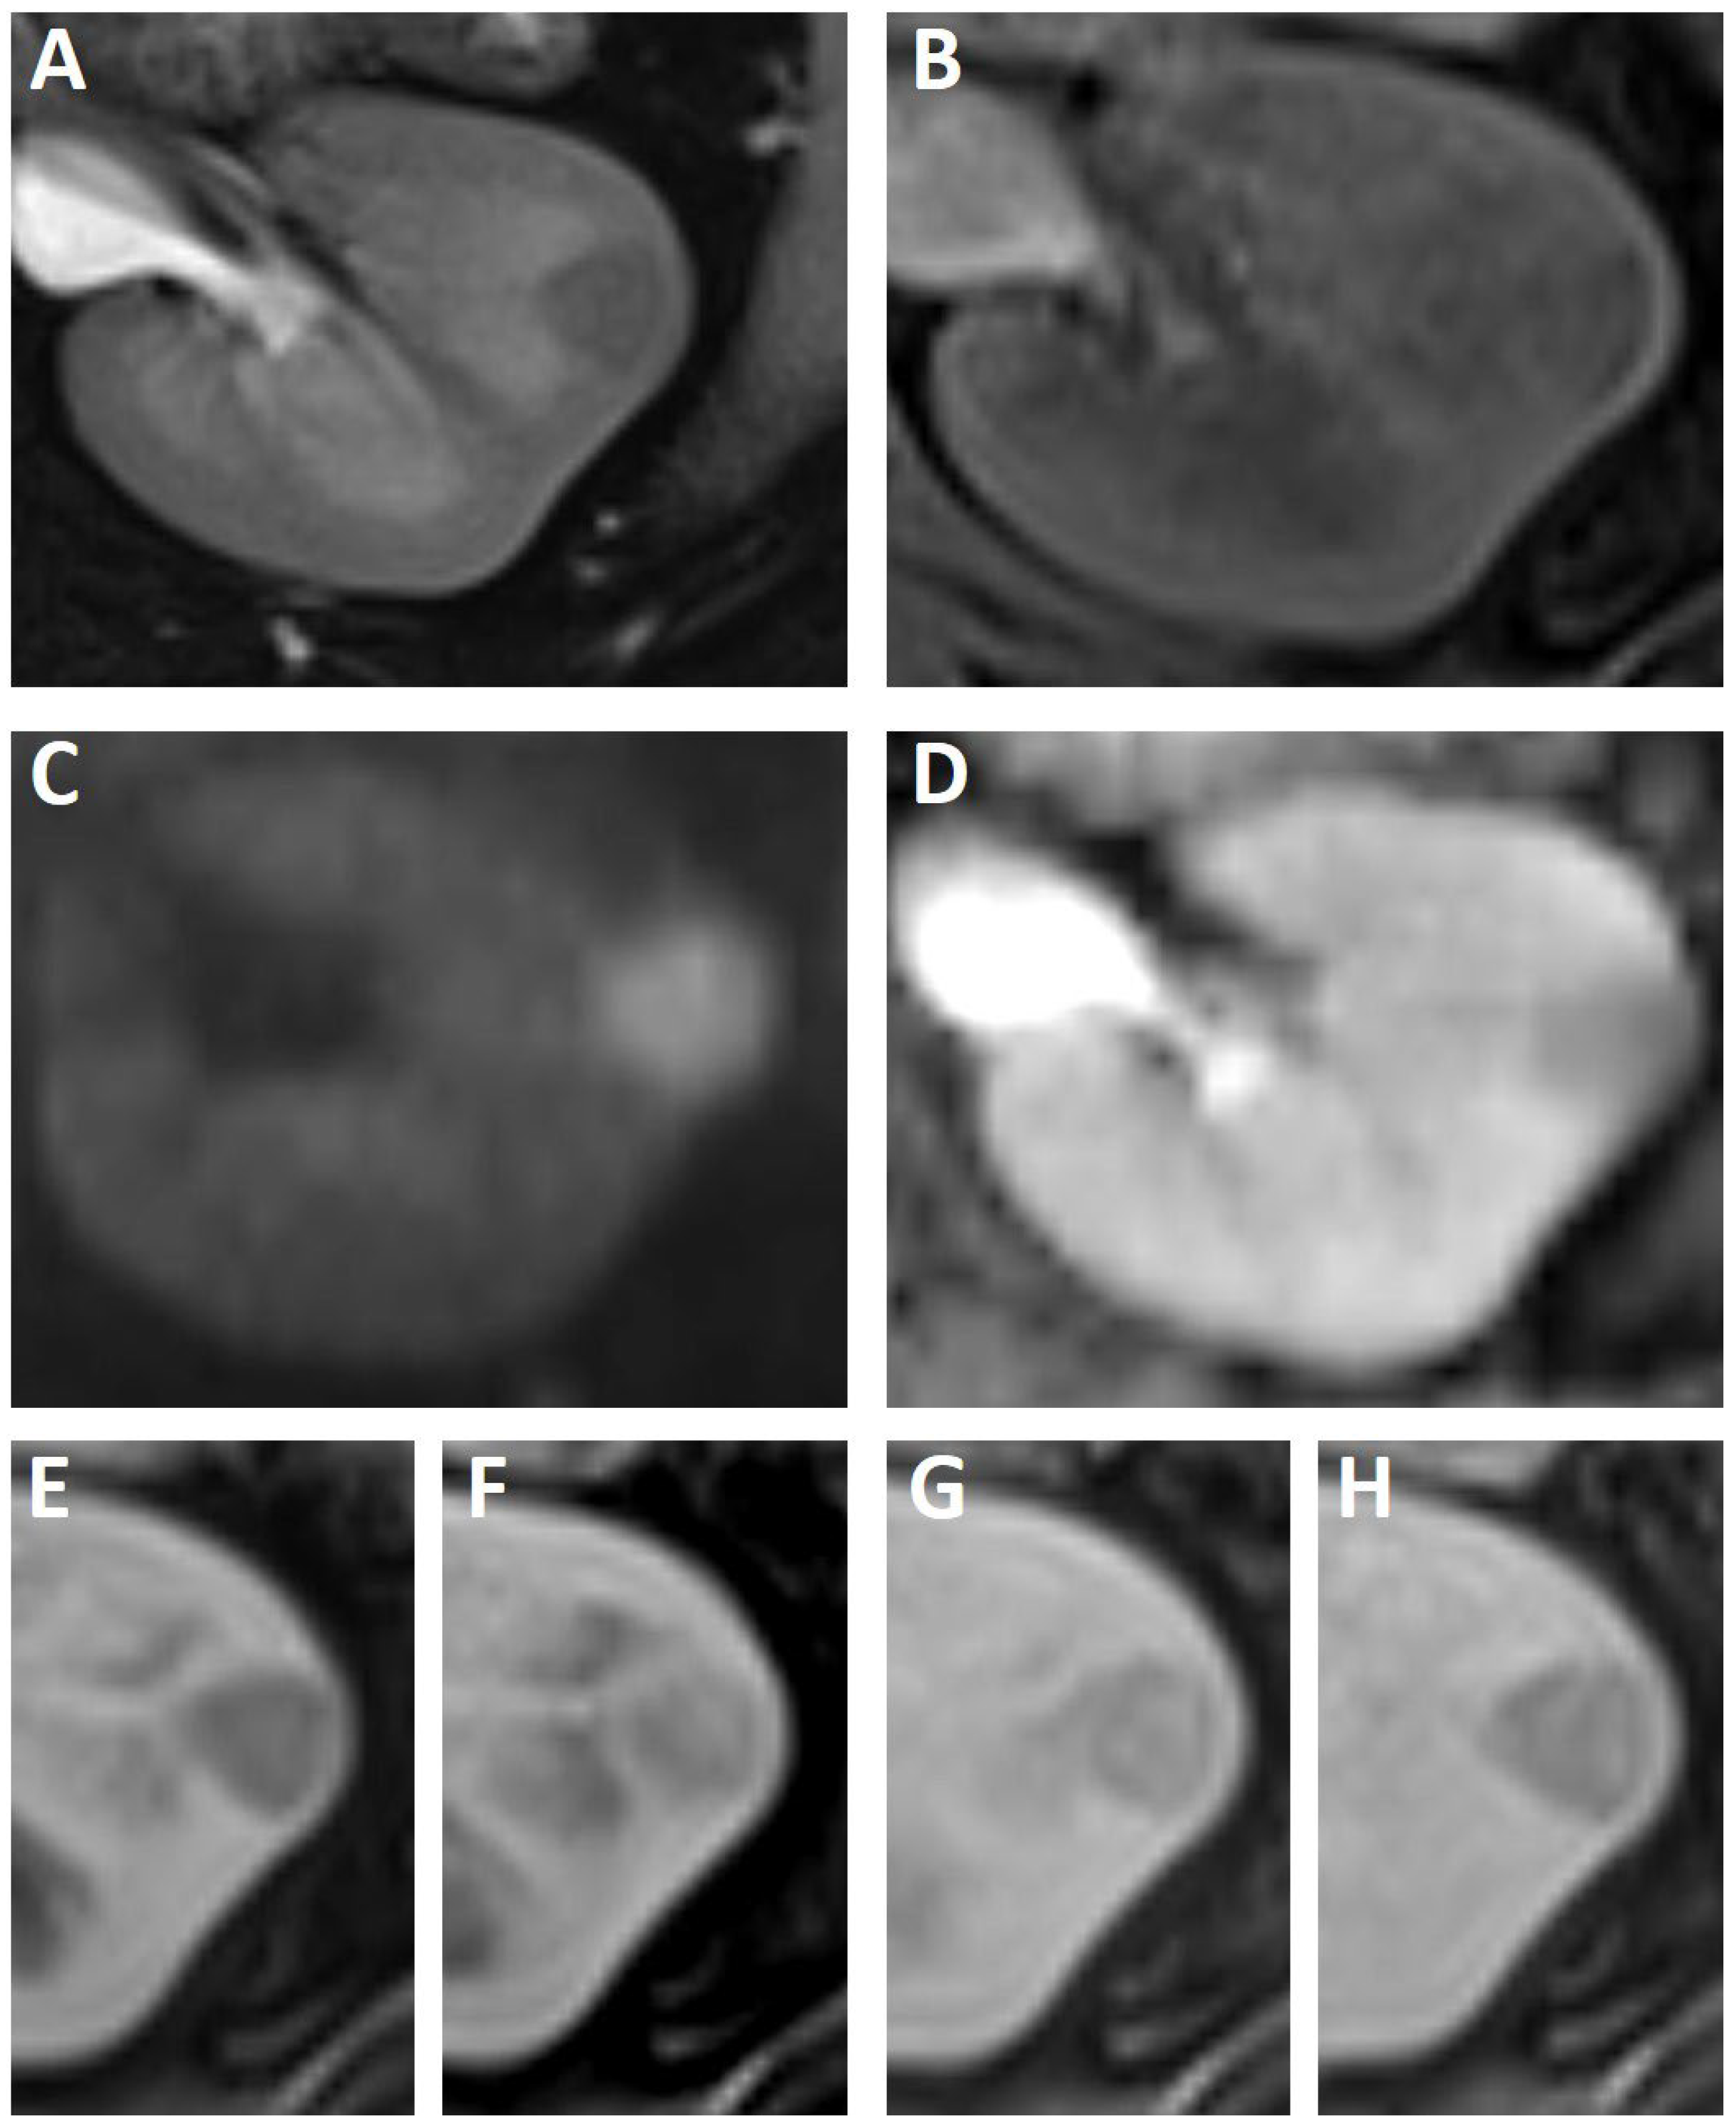

2. Case Study